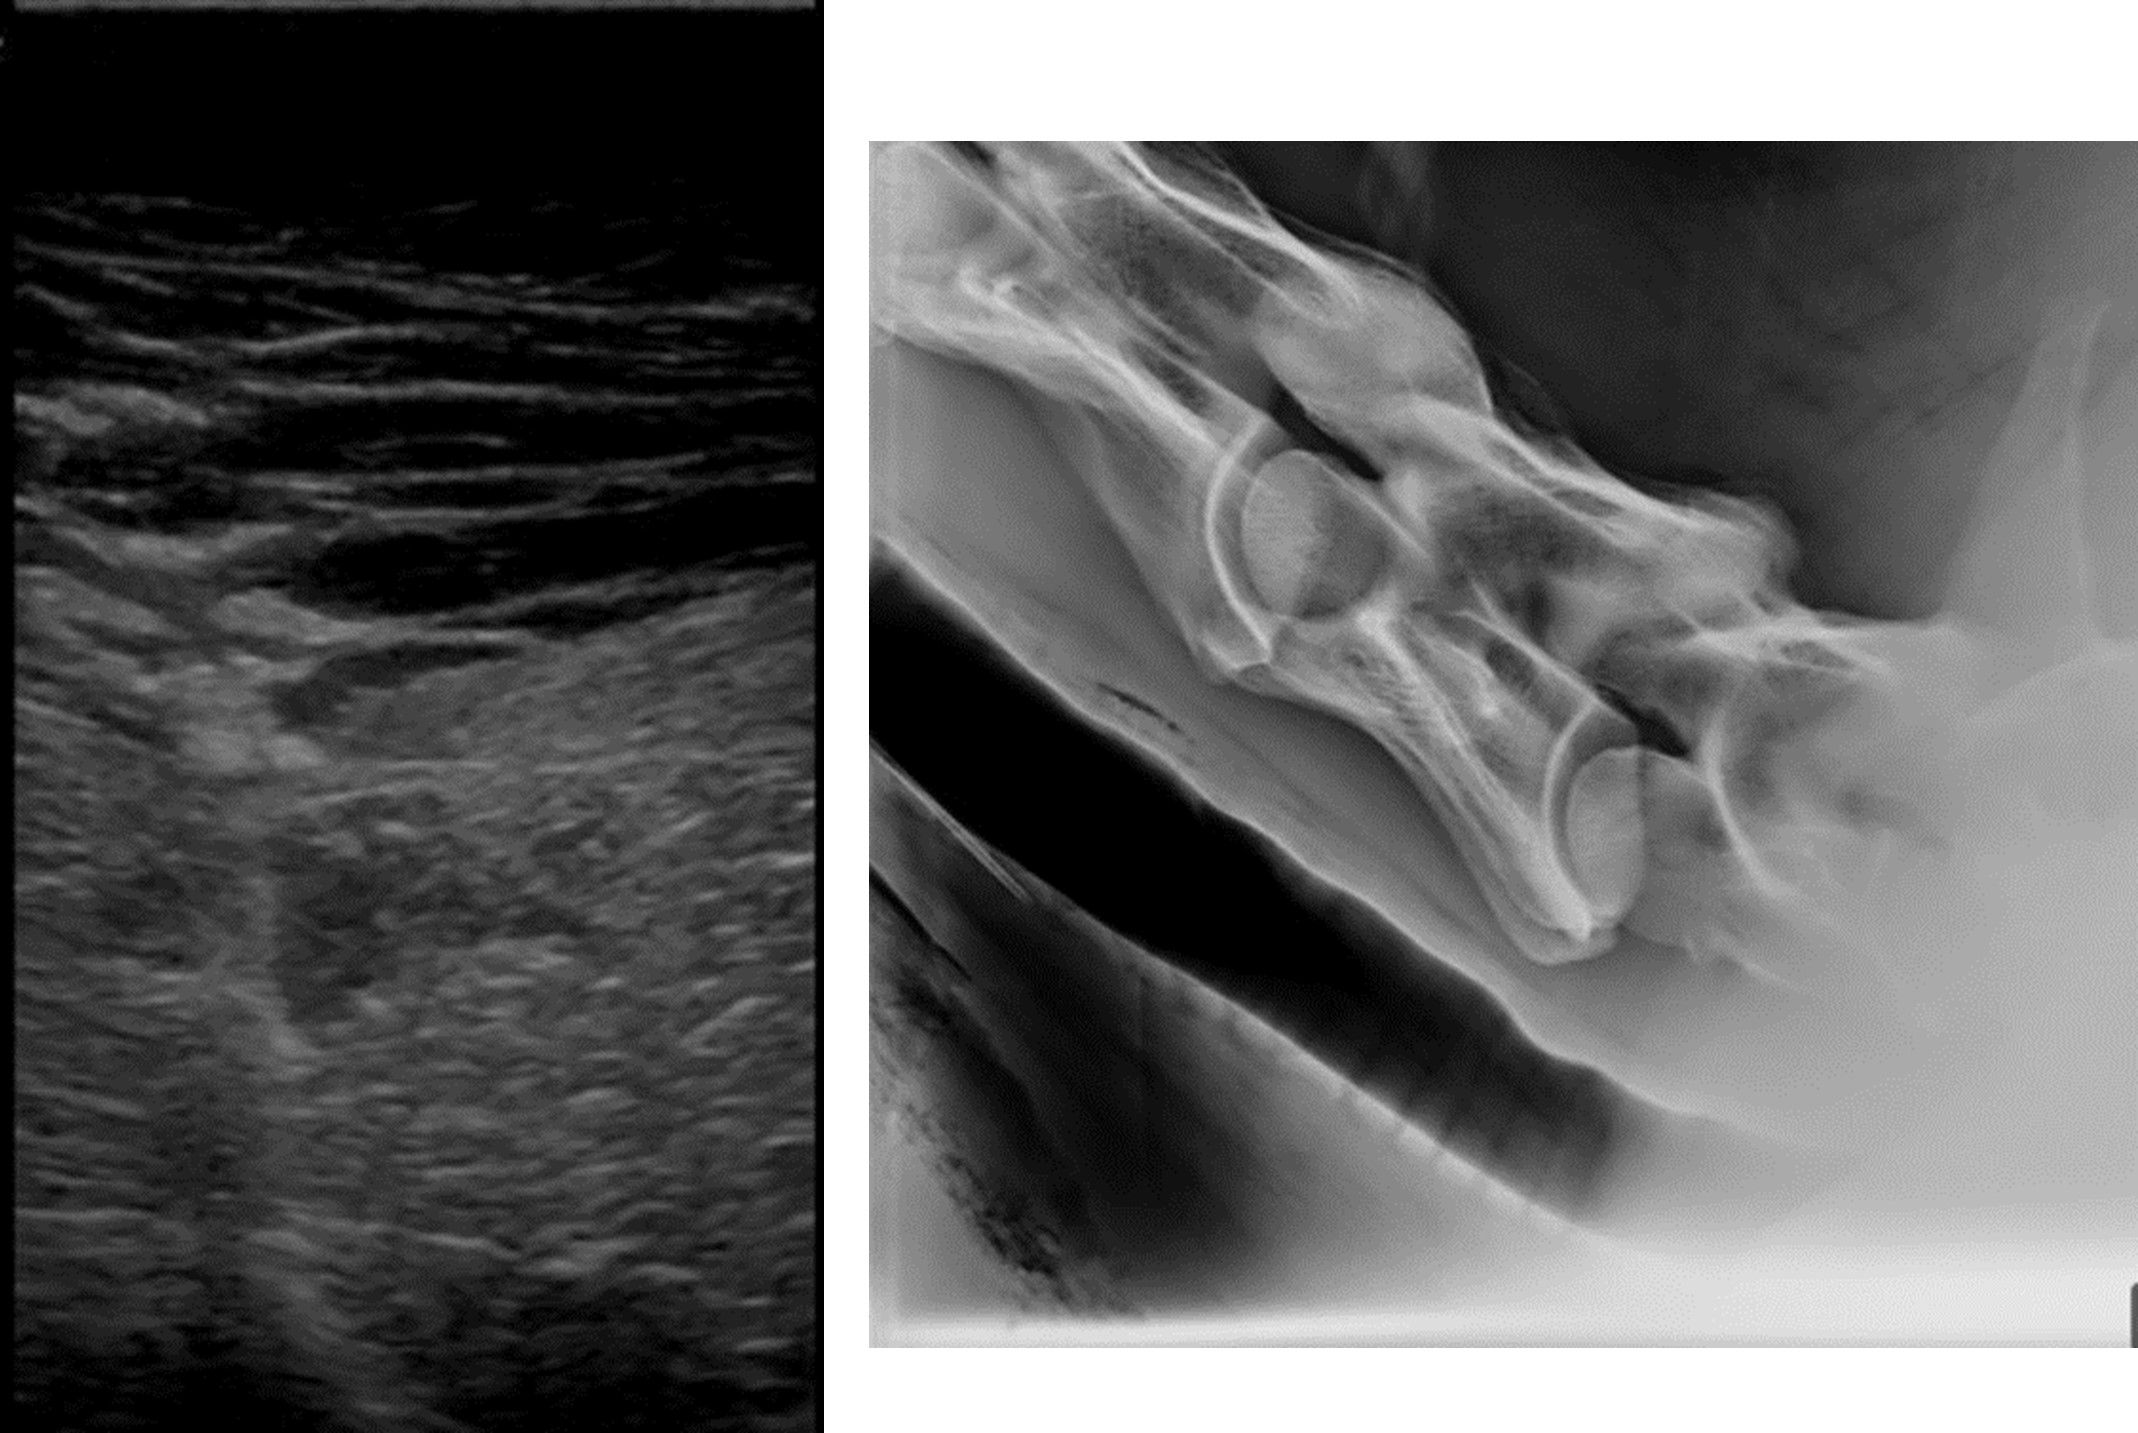

A presumptive diagnosis of clostridial myositis is often made based on clinical signs and history. Aspiration of the swollen, edematous areas reveals serosanguinous, malodorous fluid with or without gas. Gram stain of the aspirated fluid often reveals gram-positive, spore-forming rods.4 Exudate and/or affected muscle tissue can be submitted for fluorescent antibody testing, immunohistochemistry, anaerobic culture, and/ or polymerase chain reaction for confirmation and species distinction, which may affect prognosis.4 Clinicopathologic abnormalities are nonspecific and consistent with a septic process, and elevated muscle enzymes may be noted but often do not correlate with the degree of myonecrosis.1 Ultrasound and/or radiographs of the area will show areas of subcutaneous edema and gas under the skin (Figures 1A and 1B).